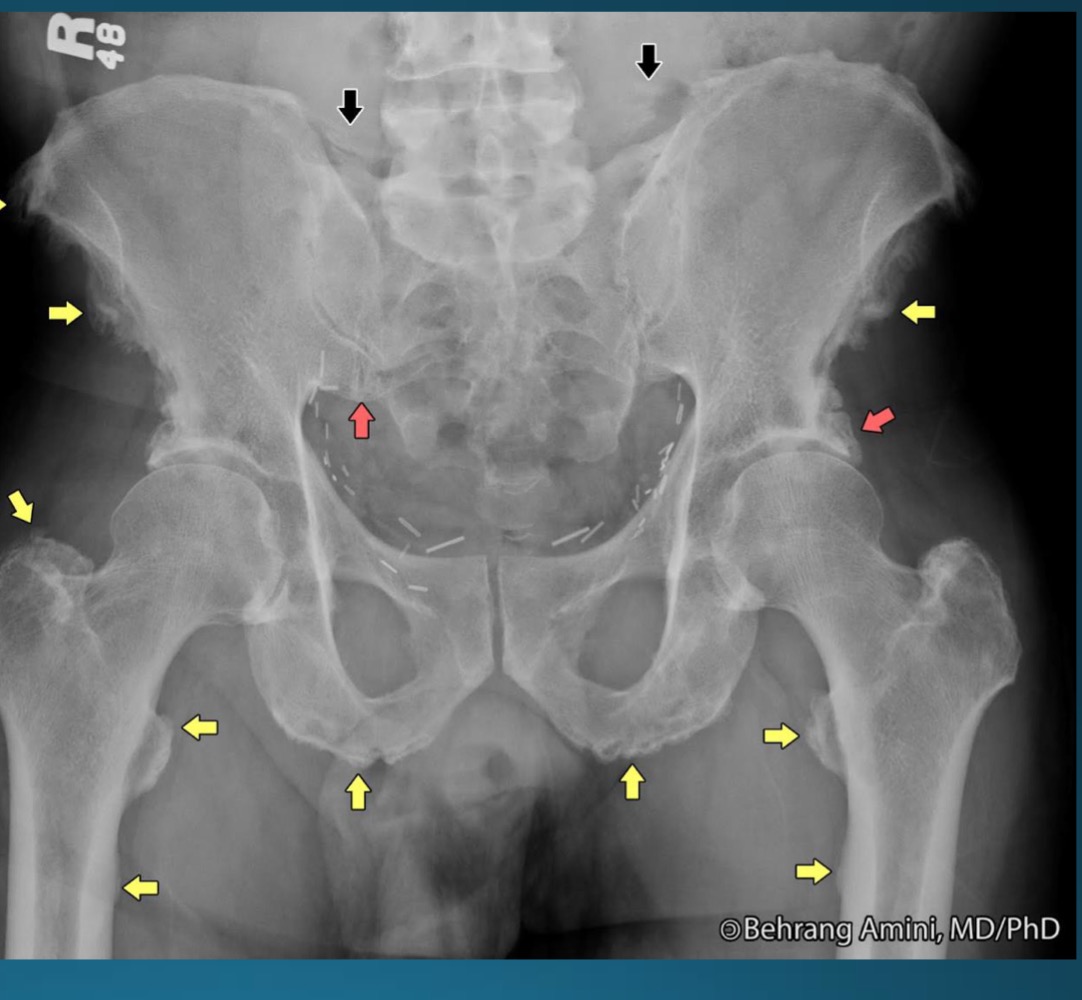

what is the diagnosis?

AS

sacroilitis

what are the signs seen in this image? what diagnosis would you make

rosary bead appearance (wavy appearance in SI joint area)

star sign (at superior angle of SI joint)

what are the signs seen in this image? what diagnosis would you make?

ghost joint (line in SI joint area but no space)